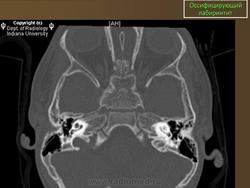

Оссифицирующий лабиринтит